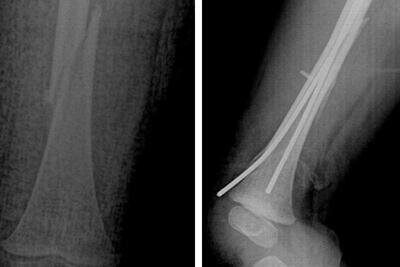

Рентгеновский снимок © Пресс-служба Министерства здравоохранения Московской области

В Московскую областную детскую клиническую травматолого-ортопедическую больницу (МОДКТОБ) поступил 2-летний ребенок с жалобами на отек и деформацию правого бедра. Врачи диагностировали у него закрытый перелом бедренной кости со смещением отломков. Травму пациент получил, прыгая на батутах.

«Мы провели успешное хирургическое лечение. В ходе операции были сопоставлены и фиксированы все отломки кости в анатомически верное положение. После срастания перелома установленные металлические конструкции, соединяющие сломанную кость, будут удалены», - рассказал главный врач МОДКТОБ Александр Григорьев.